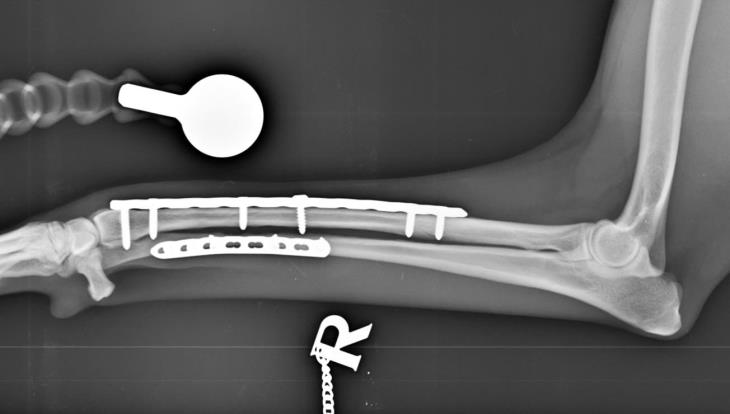

The patient presented 10 weeks post-operatively for routine radiographs which demonstrated excellent osseous union and no implant-associated complications.

No lameness nor discomfort were detected, and the patient has now returned to her normal activity levels.